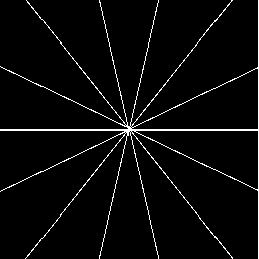

In this section we report the results of several tests run on simulated under-sampled data obtained by synthetic (phantoms) and full resolution MRI images. The under-sampled data are obtained as where is the full resolution image and is the under-sampling Fourier matrix, obtained as in (5). The under-sampling masks, analyzed in the next paragraphs are: radial mask (), parallel mask () and random mask (). In figure 1 we represent an example of each mask with low sampling rate , measured by the percentage ratio between the number of non-zero pixels and the total number of pixels :